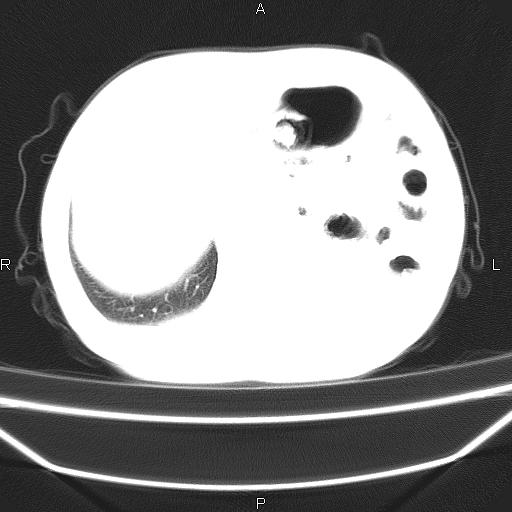

患者,男。50岁。近几日有咳嗽症状,无其他不适,既往病史无,考虑膈疝。请前辈们看看指导指导。

膈膨升,左下肺通气不良,膈肌好像还完整。

考虑左侧膈疝。

左侧膈疝。

符合隔膨升,膈肌较完整。